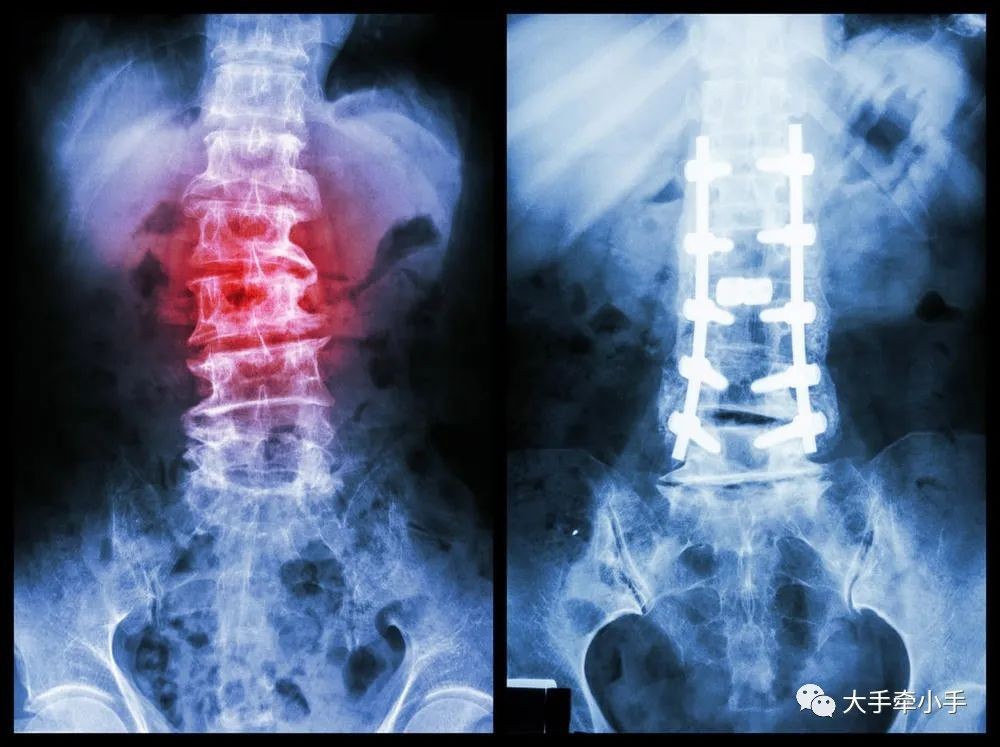

脊柱侧弯是一种脊柱的三维畸形,包括冠状位、矢状位和轴位上的序列异常。一般以拍摄站立位的全脊柱X线片为诊断依据,如果正位X线片显示脊柱有大于10度的侧方弯曲,即可诊断为脊柱侧弯。

轻度的脊柱侧凸可以观察,严重者需要手术治疗。还是那句话,关键是要早发现、早治疗。

8 怎样的脊柱侧弯需要矫正?怎么矫正?

不是所有的脊柱侧弯都要戴支具,不同的病因,处理方法是不一样的,要制定合理的治疗方案。

首先,支具只对特发性脊柱侧弯有用,对于那些先天性的脊柱侧弯,单纯地戴支具不会有任何效果。

对于特发性脊柱侧弯来说,如果侧弯幅度在20度以内的,可以暂时不用佩戴支具,通过平时注意姿势体态来控制,并且需要长期观察。

侧弯幅度在20度到45度之间的特发性脊柱侧弯,则可以通过佩戴支具来辅助治疗,这种情况如果单靠平时注意体态调节,已经没多大作用了。

首先,说一个常识——脊柱侧弯是不可逆的,也就是只要弯了,就不可能完全变正,所有的治疗矫正,都是为了防止进一步侧弯。